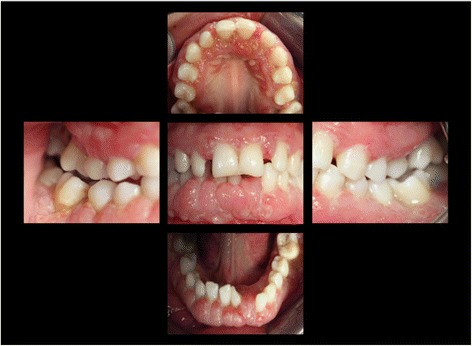

Figure 5.

Intraoral photographs at the age of 16 years: three years following conventional quadrantwise supra- and subgingival debridement without any supportive periodontal therapy.

The supra- and subgingival debridement of all teeth was performed under local anesthesia within 24 hours and maxillary right and both mandibulary first molars were extracted. The patient was given oral hygiene instruction. Adjunctive antimicrobial therapy included systemic administration of amoxicillin (500 mg tid) and metronidazole (400 mg tid) and twice daily rinsing with 0.2% chlorhexidin digluconate for two weeks [15-17]. Eight weeks following the treatment the gingival hyperplasia, pocket probing depth and bleeding on probing were markedly reduced (Figure 6). The patient received supportive periodontal therapy every three months (Figure 7). At a follow-up examination at the age of 18 years, there were only minimal signs of residual gingival hyperplasia (regio 32–42) and signs of arrested periodontitis (Figures 8 and 9). A microbiological analysis showed the intraoral absence of Aggregatibacter actinomycetemcomitans, Porphyromonas gingivalis, Prevotella intermedia and Treponema denticola. Interestingly, the clinical signs of type I PLG deficiency at the ear, urogenital tract and upper respiratory tract and the eyes showed positive changes at the same time following periodontal therapy. The situation proved to be stable since (Figure 10) and at the age of 19 it was decided to improve estethics in the upper anterior region by direct restaurations with composite (Filtek Supreme XTE, 3 M Espe, Seefeld, Germany). In the lower anterior region direct composite restaurations (Filtek Supreme XTE, 3 M Espe, Seefeld, Germany) in combination with glas fiber (Ribbond THM, Ribbond, Seattle, USA) reinforced composite pontics were used (Figures 11, 12 and 13).